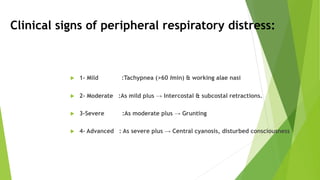

This document discusses respiratory distress and respiratory distress syndrome in neonates. It defines respiratory distress and describes the clinical signs. Various pulmonary and non-pulmonary causes are outlined. Respiratory distress syndrome, also known as hyaline membrane disease, is described in detail, including risk factors, pathophysiology, clinical presentation, investigations, complications, prevention, and treatment approaches like surfactant administration and nasal continuous positive airway pressure. The prognosis depends on gestational age and quality of care provided.